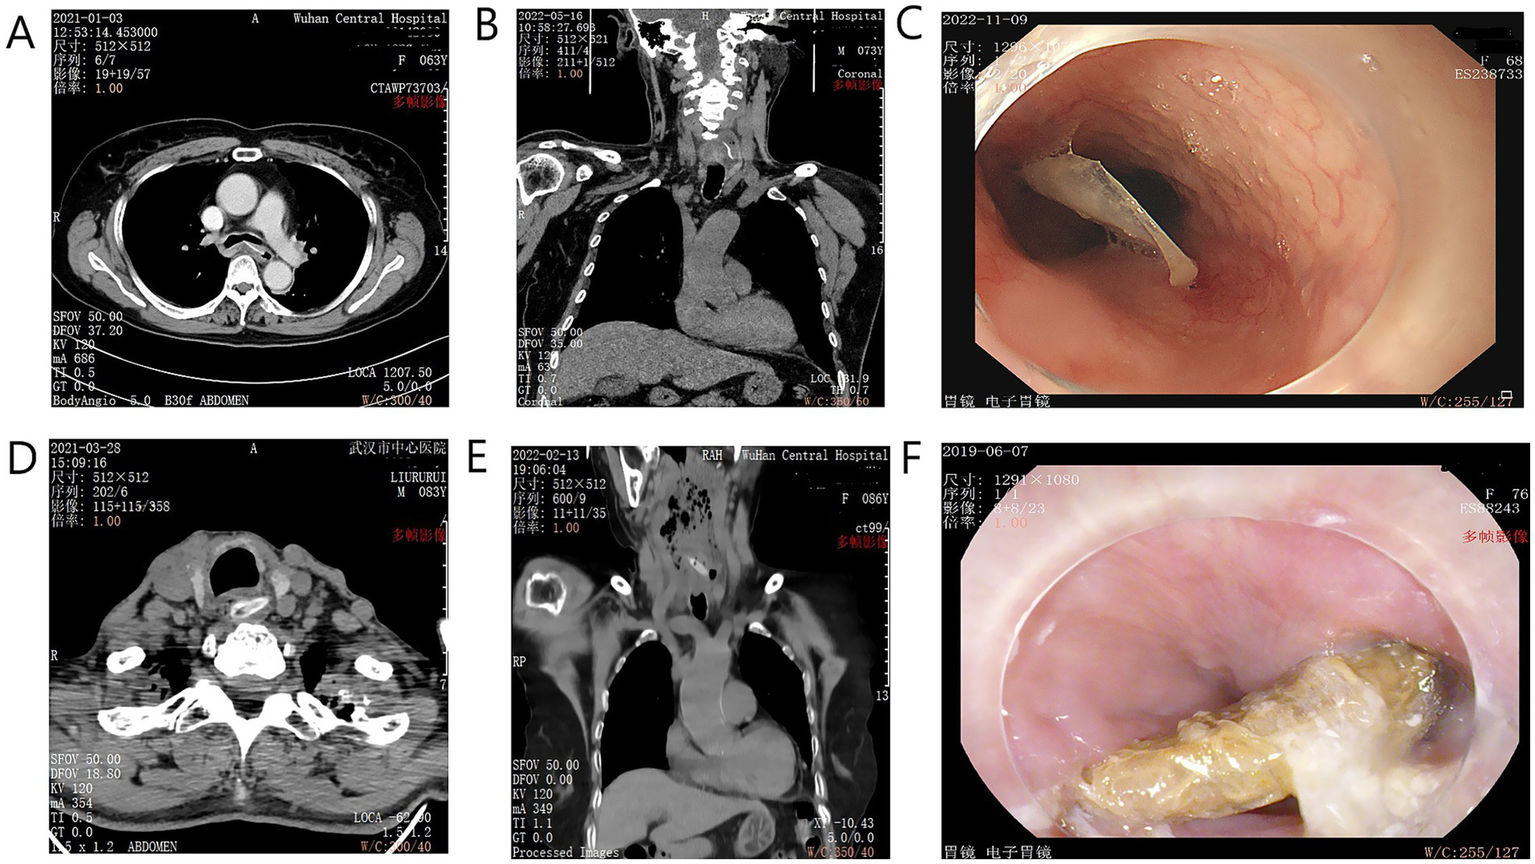

The types of sharp objects included jujube pits, fish bones, bullfrog bones, poultry bones, and pig bones. Fish bones (n = 35, 60.3%) and jujube pits (n = 15, 25.9%) were the most common. The incidence rates of bullfrog bones, poultry bones, and pig bones were 2 (3.4%), 4 (6.9%), and 2 (3.4%), respectively (examples are shown in Figure 2).

Figure 2

Examples of sharp foreign bodies identified by CT and endoscopy. (A) Axial CT scan showing a fish bone penetrating the esophageal wall. (B) Coronal CT view of a similar injury. (C) Endoscopic view of an impacted fish bone. (D) Axial CT showing a jujube pit in the cervical esophagus. (E) Coronal CT view of an impacted jujube pit causing peri-esophageal inflammation. (F) Endoscopic view of a large, impacted jujube pit.